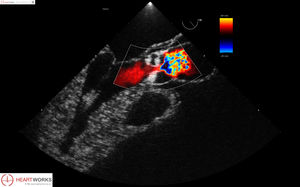

... Los módulos de patología de HeartWorks para la TTE y la TEE han sido creados para facilitar la evaluación ecocardiográfica de pacientes con alteraciones estructurales y hemodinámicas. Este módulo incluye ...

Inventive Medical Limited